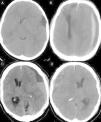

ResultadosLa serie consta de 32 varones y 10 mujeres con una edad media de 29,3±8,9 años (intervalo 4-39). El período transcurrido entre el traumatismo y el inicio de la sintomatología fue de 33,4±9,7 días (intervalo 19-95). Los principales síntomas de presentación fueron la cefalea (59,5%) y las crisis comiciales (21,4%), y los factores predisponentes más frecuentes fueron tener implantada una derivación ventrículo-peritoneal en 5 (11,9%) casos y los trastornos hematológicos en otros 5 (11,9%) pacientes. El hematoma fue derecho en 21 pacientes (50%), izquierdo en 19 (45,3%) y bilateral en los restantes 2 (4,7%). Se produjeron 2 complicaciones postoperatorias: un caso de recidiva y un hematoma subdural agudo sobre la cavidad del hematoma. No se produjeron muertes relacionadas con el tratamiento.

ResultsOf the 42 cases analysed, 32 were males and 10 were females, and the mean age at diagnosis was 29.3±8.9 years (range: 4 to 39 years). The mean interval from trauma to appearance of clinical symptoms was 33.4±9.7 days (range: 19 to 95 days). The main symptoms were headache (59.5%) and seizures (21.4%), and the most frequent predisposing factors were ventriculoperitoneal shunting in 5 (11.9%) patients and haematological disorders in another 5 (11.9%) cases. CSDH was right-sided in 21 cases (50%), left-sided in 19 cases (45.3%) and bilateral in the remaining 2 patients (4.7%). Postoperative complications occurred in 2 patients (1 recurrence and 1 acute subdural haematoma).